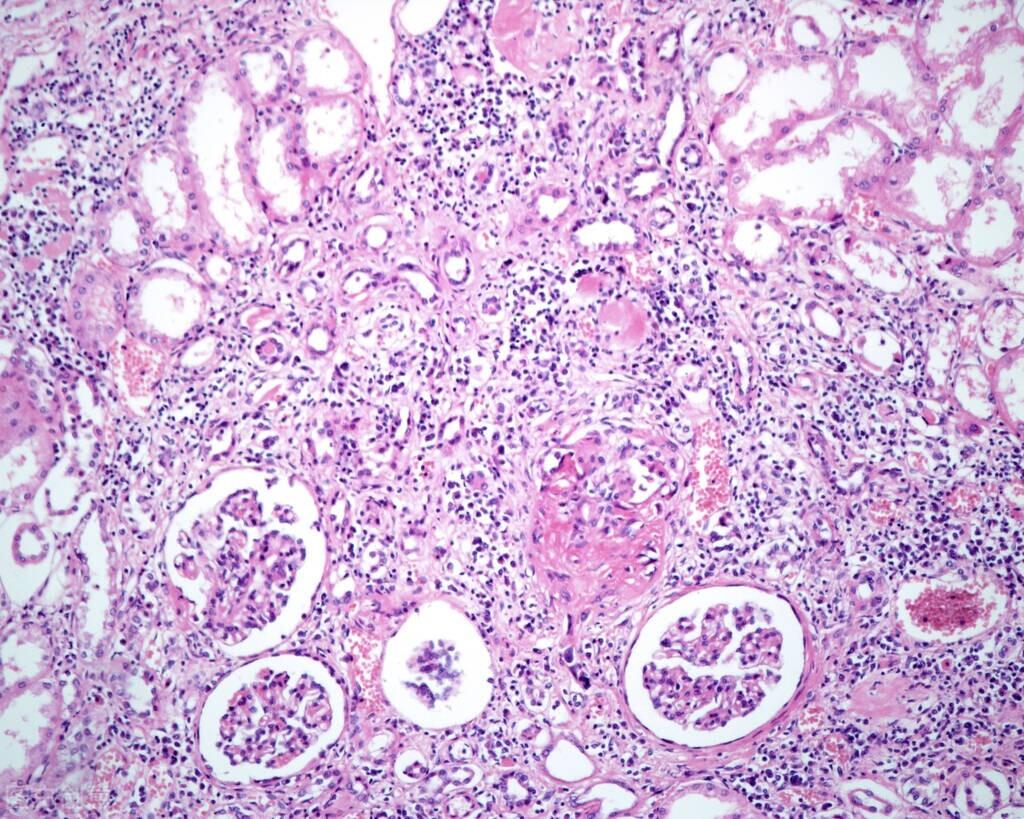

#爱乐养生指南# 患血管炎很好治吗,实际上不是这样的,血管炎还是挺不易治的,这是一类对身体伤害较大的血管疾病,随时随地会出现生命威胁,因此积极治疗血管炎非常重要的,依据现在的医药学水平,该怎么治疗血管炎,医治血管炎的方法大致有几种呢,大致有一般医治、物理治疗、药物治疗3种,病患能够依据自身的实际病况来挑选。